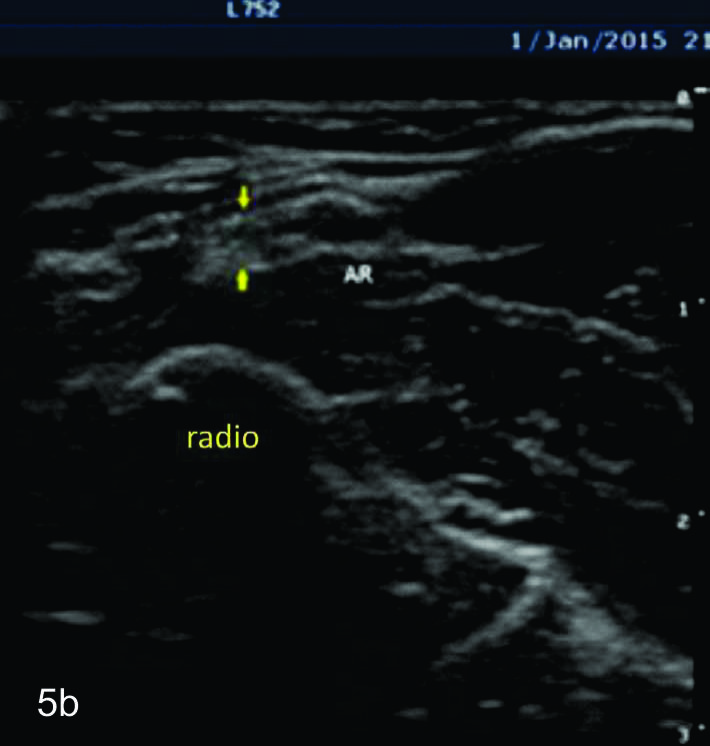

Figura 5

Nervio radial superficial

Cortes axiales del nervio radial superficial, desde su origen a nivel del codo como rama terminal del nervio cubital hasta la zona distal visible con el equipamiento empleado en tercio distal del antebrazo. Se identifica el mismo señalado por flechas amarillas, localizado adyacente a la arteria radial (AR).